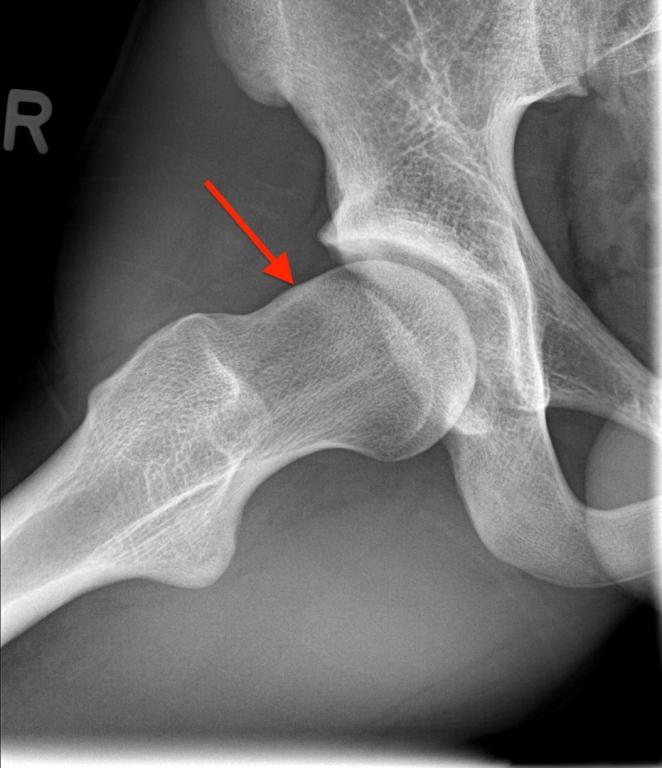

Klachten van het heupgewricht komen relatief vaak voor bij (jong)volwassenen. Een groot deel van deze klachten worden veroorzaakt door de anatomie van het heupgewricht, die bepaald wordt door aanleg en deels door omgevingsfactoren. Het tijdig diagnosticeren van belangrijke heuppathologie door medici en paramedici is essentieel voor zowel behandeling als prognose. Voldoende theoretische en praktische kennis is daarom van groot belang. In dit Physios-artikel wordt aandacht besteed aan de heupanatomie, diagnostiek (met o.a. lichamelijk en aanvullend onderzoek), behandeling en prognose van heupdysplasie en het femoroacetabulair impingement (FAI). Ook de laatste wetenschappelijke inzichten in het diagnostisch en therapeutisch traject komen aan de orde. Voor de fysiotherapeut is met name het diagnostische en conservatief-therapeutische deel relevant. Door kennis hiervan kan de fysiotherapeut tijdig heupgerelateerde problematiek herkennen, de juiste conservatieve therapie instellen en zo voor de patiënt het verschil maken.